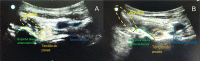

Objective To describe and evaluate the accuracy of the pericapsular nerve group (PENG) block technique with no ultrasound guidance. Method Series of 40 infiltrations in patients with hip pain undergoing outpatient follow-up in the hip surgery group or admitted to the emergency room from a hospital in São Paulo, SP, Brazil. The hip PENG technique was guided by palpable anatomical pelvic structures, with no ultrasound orientation for needle positioning, using the equipment only to check the correct location after an unguided puncture. Results In the 40 hips infiltrated from 35 patients with a mean age of 59.2 years, the success rate was 85%. Among the mispositioned cases, 71.4% occurred in the first 13 applications and 28.6% in the subsequent 27 applications. In all patients, the neurovascular bundle was in the medial third of the pen-made demarcation. Even in cases with a failed needle location, the distance from the neurovascular bundle was safe. A single adverse effect occurred, with spontaneous improvement of the femoral nerve apraxia within two days. Conclusion Unguided PENG block is a viable technique for a physician knowledgeable about its application in services with no ultrasound availability.